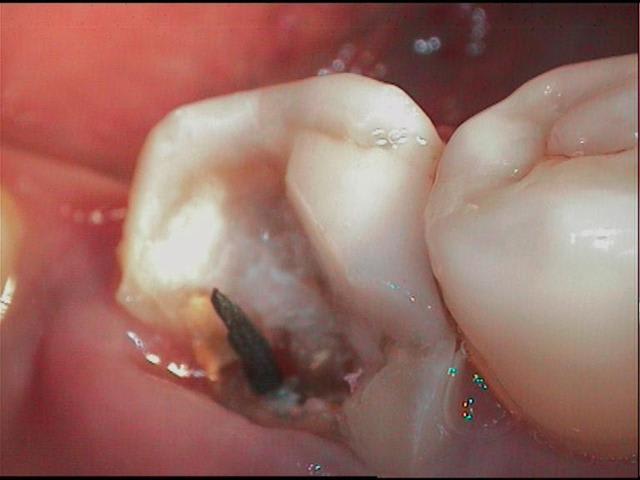

en déposant délicatement le compo, je trouve donc ça (photos) et c'était plutôt bien fait, j'imagine que le prat a craint d'avoir trop de contraintes canalaires avec un ancrage différent, moralité les contraintes ce sont accumulées au tiers cervical et c'est là que ça a cassé.

l'image radio était trompeuse et le probleme n'était pas endo.

donc, immédiatement assainissement et prov rapide, et remission des signes en 15j